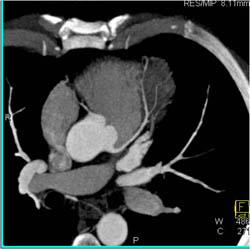

Diseased LAD